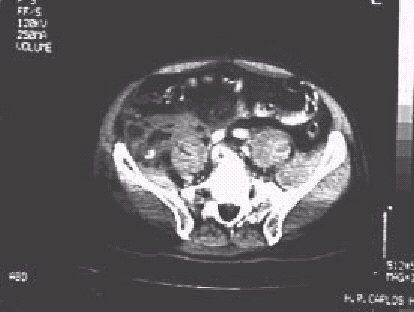

Figura 8.—El mismo caso de la figura anterior (Imagen.-6). Se aprecia próximo al músculo Ilíaco derecho, un punto de alta atenuación que corresponde a extravasación de contraste por el punto de sangrado pélvico.